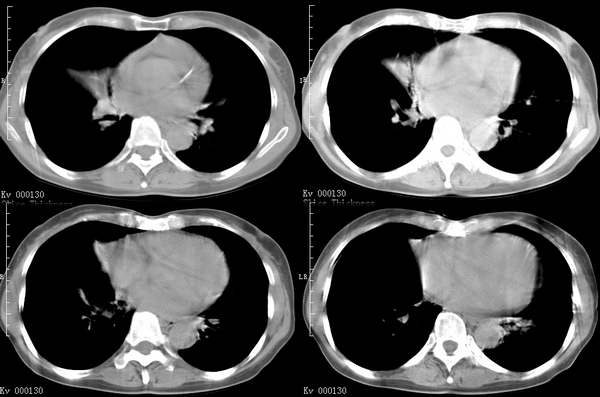

咳嗽6月低热1月!

右上叶背段及左下叶见斑片状密度不均模糊影,右中叶支气管狭窄,中叶密度增高,体积缩小.纵隔未见明确淋巴结.结论:1、两俩结核,右中叶支气管内膜结核,并中叶肺不张。2、两肺炎;右中心型肺癌,并阻塞性肺不张。

右肺上叶尖后段及左肺舌叶 下叶见斑片状密度不均模糊影,右中叶支气管狭窄,中叶密度增高,体积缩小.纵隔未见明确淋巴结。考虑:双肺结核伴右侧中叶不张。

纵隔淋巴结增大,中叶肺不张.肺癌可能性大

右上叶背段及左下叶见斑片状密度不均模糊影,右中叶支气管狭窄,近端未见肿块,中叶密度增高,体积缩小.纵隔未见明确淋巴结.结论:两肺结核,右中叶支气管内膜结核,并中叶肺不张。肺纹理粗乱,有慢支表现,伴有感染存在。

ct显示病灶呈多灶性分布,主要分布在双肺上叶后段,右肺中叶及左肺下叶,右肺上病灶内可见点状钙化,纵隔内示淋巴结钙化,结合病史6个月伴低热,考虑感染性病变,结核可能大.